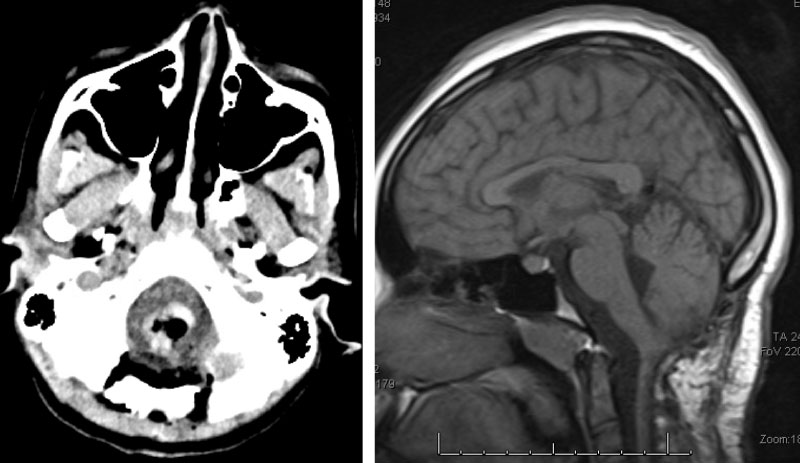

Figure 3. Immediate post-op CT (left) and two-year follow-up MRI (right).